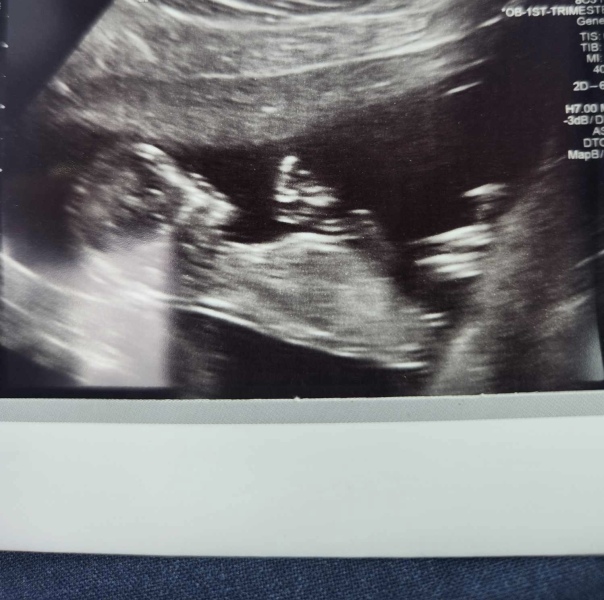

We had our scan this morning and all is well 🥰 So relived!

Also, do you know what you’re having? I want to predict girl using my limited nub theory skills ✨

Hurrah @Caroline2023! Lovely photo Smile

Congrats @Caroline2023 lovely scan picture!

Lovely scan @Caroline2023. I have mine on Friday and getting nervous.

@Caroline2023 lovely scan. I would guess that @Honeyandsunshine1 is correct with girl! I know virtually all scan pics look identical at this stage but your scan photo looks incredibly similar to mine (girl) do you have any DC already?